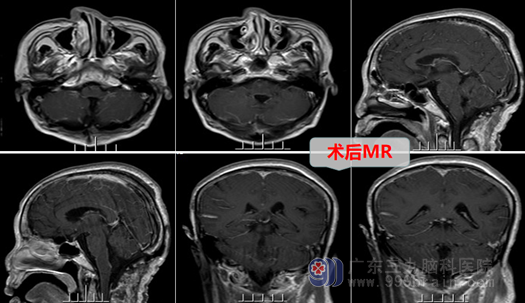

入院后,主管医生邓心情在对劳女士进行一系列相关检查,外十科在欧阳辉主任的带领下,对劳女士的病情仔细分析、讨论,认为劳女士的肿瘤大,主体位于第四脑室,与脑干关系密切,属于脑干-四脑室肿瘤,必须手术治疗,但由于肿瘤可能从脑干长出,手术风险很大。在完善相关术前准备,确认劳女士无手术禁忌症后,医生详细向其家属解释了病情,说明了手术的必要性和危险性。在征得患者及其家属的理解和同意后,外十科为其进行了“后颅窝开颅,脑干-第四脑室内占位切除术”,术中见肿瘤确实是从第四脑室底延髓背侧长出,肿瘤与脑干黏连,欧阳辉教授在显微镜放大下,剖开小脑下蚓部,沿肿瘤周边游离,精准、分块切除肿瘤,术中冰冻结果提示:低级别神经源性肿瘤(最后常规病理证实为室管膜瘤),医生如履薄冰、如临深渊,虎口拔牙,细心切除肿瘤大小约4*4*3cm,相邻脑干、血管解剖保护良好。手术顺利成功,现劳女士各方面恢复良好,无手术并发症发生。